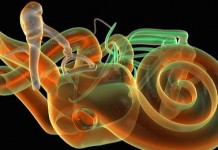

Опухоли слухового нерва

Описание Опухоль слухового нерва (акустическая неврома, акустическая невринома, вестибулярная шваннома, опухоль восьмой пары нервов) - доброкачественная опухоль, которая исходит из шванновских клеток (клеток, создающих оболочку...

Опухоли уха

Описание Опухоли уха бывают доброкачественными или злокачественными. Доброкачественные опухоли могут развиваться в наружном слуховом проходе, блокируя его и вызывая накопление ушной серы и развитие тугоухости. К...